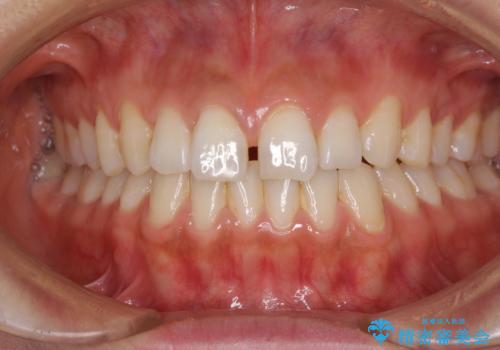

前歯の隙間をオールセラミックで閉じる

- 上の前歯の隙間を気にして来院された患者様です。

矯正治療により前歯を閉じるという治療を第一選択肢として提案しましたが、期間と費用からオールセラミッククラウンによる補綴治療を行うこととしました。

虫歯もない前歯を削ることは、処置をする者として心苦しいのですが、患者様は矯正治療は選択しないとのことだったので、オールセラミッククラウンにて補綴治療を行いました。

短期間で思い通りの仕上がりとなり、患者様には大変満足していただきました。